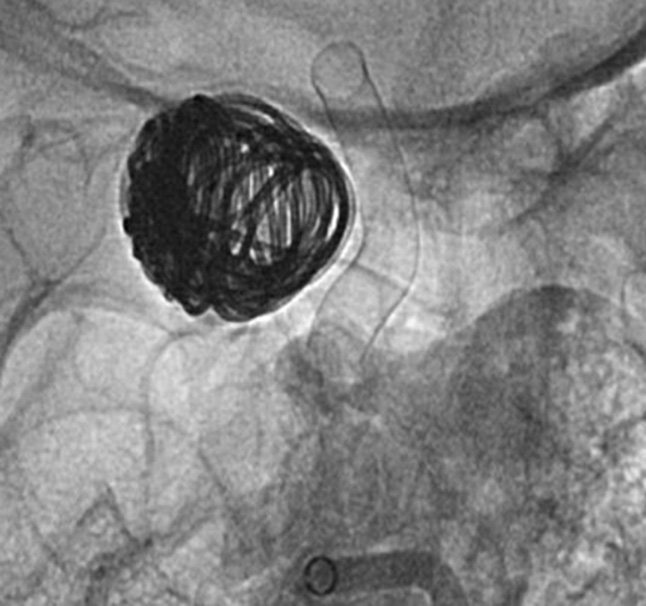

DERIVO® 2heal® Embolisation Device

After Flow Diverter Placement